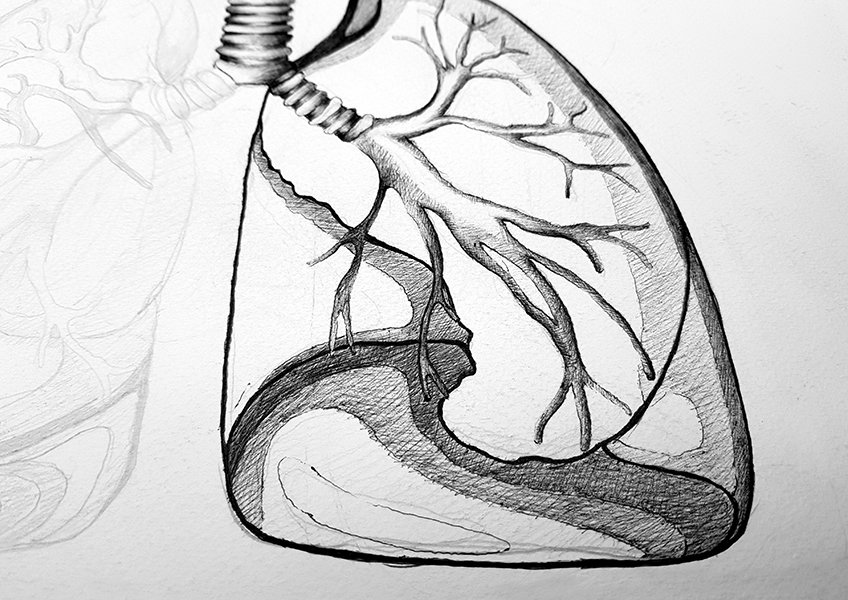

Обои для телефона с изображением лёгких человека